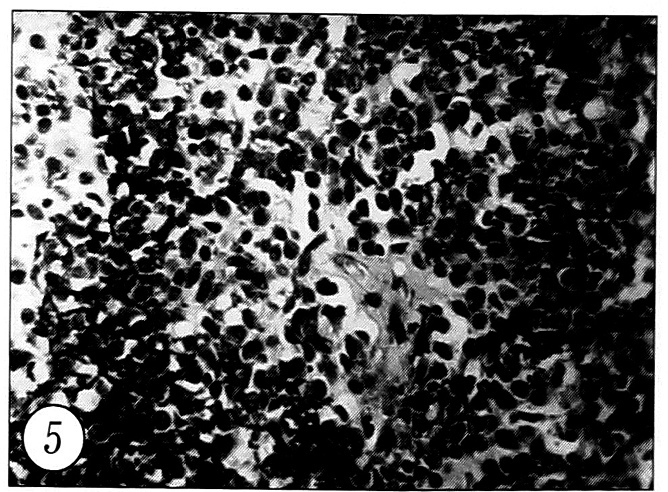

Рис. 5. Обызвествление хондробластомы с формированием характерной «сеточки» (окраска гематоксилином и эозином, ув. 300).

Во всех случаях диагноз верифицирован при морфологическом исследовании. Макроскопически ткань была серовато-желтого цвета, пропитана кровью, мягкой консистенции, с плотными крошащимися вкраплениями. Гистологически хондробластома характеризуется пролиферацией плотно расположенных хондробластов различной степени зрелости (рис. 4). Хондробласты круглой или овальной формы, с крупными ядрами, в которых ядрышки обычно не выявляются. В некоторых опухолевых клетках определяется 2-3 ядра, однако митозы немногочисленны, атипичные митозы не обнаруживаются. Поля незрелых хондробластов чередуются с участками более зрелых клеток, обычно лежащих в хондроидном матриксе. Кроме хондробластов, обнаруживаются небольшого размера многоядерные остеокластоподобные клетки — одиночные или их группы, иногда они располагаются вокруг участков микрокровоизлияний, некроза или обызвествления. Менее зрелые хондробласты по своей структуре имеют значительное сходство со стромальными клетками гигантоклеточной опухоли, а наличие в подобных участках хондробластомы многочисленных остеокластоподобных клеток может быть ошибочно расценено как гигантоклеточная опухоль [1]. Определяются соединительнотканные прослойки, делящие ткань опухоли на дольки. Характерным и важным диагностическим признаком хондробластомы является обызвествление ткани опухоли. При этом нежное сеточкоподобное отложение солей кальция происходит между незрелыми хондробластами и вокруг них (рис. 5), тогда как массивное обызвествление наблюдается в более зрелом матриксе гиалинового хряща, который подвергается дистрофическим изменениям и некрозу. В некоторых хондробластомах определяются выраженные миксоидные изменения, а также поля фибробластоподобных клеток. Иногда встречаются разной величины полости, заполненные элементами крови, — проявление вторичной аневризмальной кисты кости. Хондробластома с кистами, содержащими серозную жидкость, расценивается как кистозная форма хондробластомы.